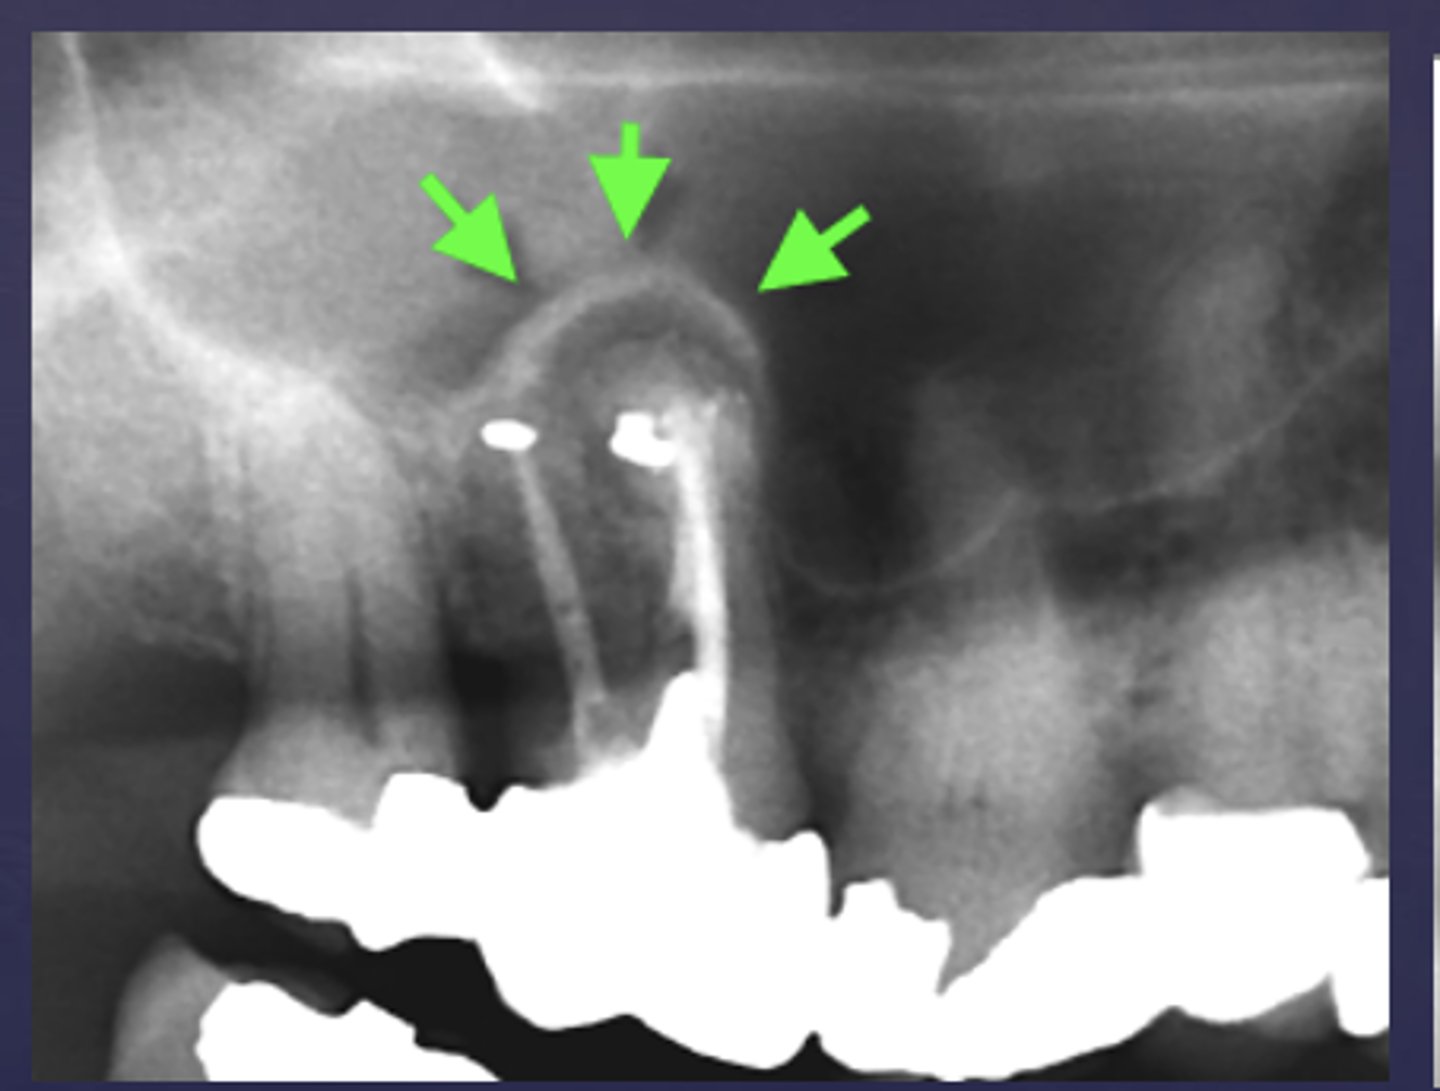

What are the arrows pointing to?

halo sign

What is a key sign of periapical inflammatory disease where there is an elevation/displacement of the floor of the maxillary sinus usually affecting maxillary posterior teeth?